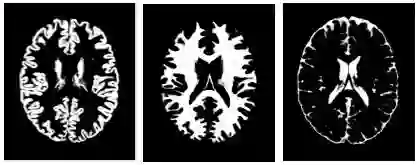

在将整个 MRI 简化为直方图时,我们忽略了关于脑结构的空间信息。为进一步提高算法的有效性和可解读性,我们使用另一种软件包 FSL FAST 将每个 MRI 分割为灰质、白质和脑脊液 (CSF)。本次分割以体素值为基础,且能够产生令人信服的结果(您可以在我们的 Colab 笔记本中对其进行研究)。

不同的脑组织分割掩膜。从左至右依次为灰质、白质和脑脊液 (CSF) 掩膜